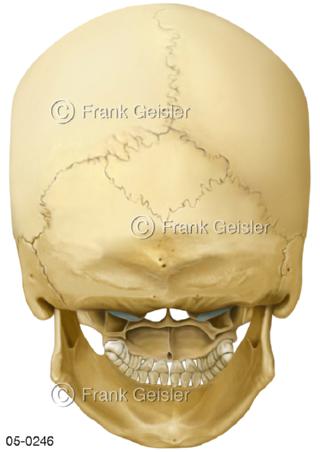

Bildergalerie Skelettsystem

Bilder zum Skelettsystem zeigen die Stützstruktur des menschlichen Körpers, die Knochen, eine besonders harte Form des Bindegewebes und Stützgewebes, welche das menschliche Skelett bildet, die Knochen des Stammes, der Extremitäten sowie der Gelenke